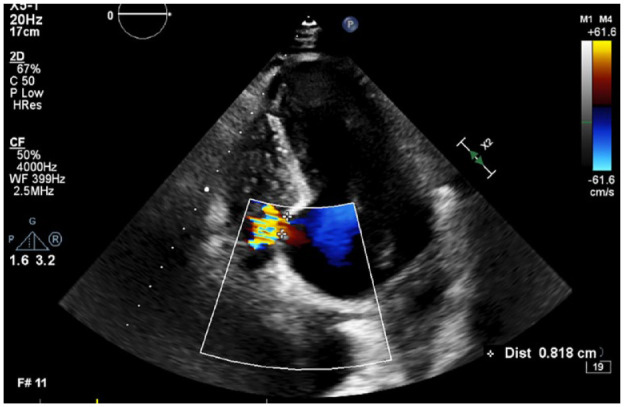

Ventricular septal defect (VSD) represents a severe complication that may manifest after a myocardial infarction (MI), typically occurring between 2 and 7 days later. Due to advancements in reperfusion management, the incidence of VSDs after MI has become very rare, occurring in approximately 0.2% of MIs. The current guidelines recommend urgent post-infarction VSD (PI-VSD) closure. We report a case of a patient with a VSD, which was diagnosed 2.5 years after MI. At the time of acute inferior MI, the patient was managed with primary percutaneous intervention in the culprit artery, and 1 month later coronary artery by-pass grafting (CABG) was completed. Twenty and thirty months after AMI patient presented with ventricular tachycardia (VT). Following the second VT episode patient was hospitalized for further examination. Echocardiography revealed the presence of VSD at the site of inferioseptal wall aneurysm. An ICD was implanted owing to recurrent malignant rhythm disorders. In conclusion, although the PI-VSD might have been overlooked and the patient missed the chance of concomitant CABG and VSD repair, this case has reached a 3-year survival, which appears to be the longest survival recorded in a medically treated patient with PI-VSD.